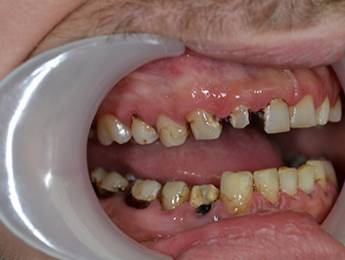

27 éves páciensünk egész életében rettegett a fogorvosi beavatkozásoktól. Az összes foga elszuvasodott. A legkárosodottabb fogak gyökérkezelése és a szuvasodásainak megszűntetése után 26 fémkerámia koronát kapott a páciens. Erre a kezelésre is nagyon büszkék vagyunk. 2 hét leforgása alatt sikerült jelentős mértékben javítanunk a páciensünk mosolyán, önbizalmán és mióta velünk talalákozott, már a fogászati kezelésektől sem fél annyira!